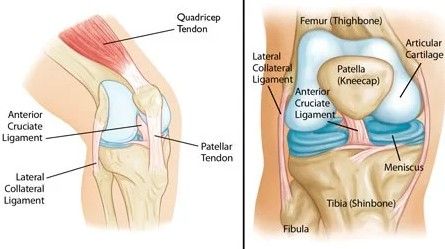

آرتروز زانو یک بیماری مزمن و التهابی است که منجر به تخریب و آسیب در سطح مفصل زانو میشود. در این بیماری، درجه فرسایش و سایش سطح غضروف زانو افزایش مییابد و باعث درد، سفتی و محدودیت حرکت در مفصل میشود. درمان آرتروز زانو معمولاً به مدیریت علائم، کاهش التهاب و افزایش عملکرد مفصل متمرکز میشود. در ادامه، تمرینات و راهکارهایی که ممکن است در مدیریت و کاهش علائم آرتروز زانو مفید باشند را بررسی خواهیم کرد:

1. تمرینات تقویتی: تمرینات تقویتی عضلات اطراف زانو میتوانند استحکام عضلات را افزایش داده و جلوی تنش و فشار اضافی روی مفصل زانو را بگیرند. تمرینات ایزوله عضلات پشت ران مانند انقباض و رها سازی عضلات کوادریسپس و همچنین تمریناتی برای استحکام عضلات پشت زانو میتوانند مفید باشند.

1. تمرینات تقویتی عضلات: تمریناتی که به تقویت عضلات اطراف زانو میپردازند، میتوانند فشار روی مفصل زانو را کاهش داده و استحکام و پایداری مفصل را افزایش دهند. تمریناتی مانند انقباض عضلات کوادریسپس (عضلات جلو ران)، انقباض عضلات ایزومتریک (بدون تغییر طول عضلات) و تمرینات ایزوله عضلات پشت ران میتوانند مفید باشند. همچنین، تمرینات تقویتی عضلات کمر و شکم نیز میتوانند به حفظ تعادل و استحکام کل بدن کمک کنند.